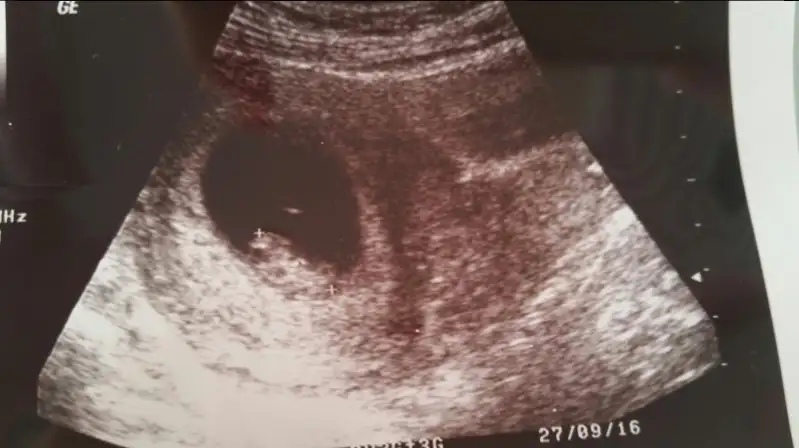

benim keseme çok benziyor :) erkek bence.kizlar bu da minnagiimm :)) ustteki minnagiimm alttaki yolk kesemizz :)) sizce cinsiyeti ne olabilir :))

ben de oyle hissediyorumm :)) Rabb im hayirli evlat nasip etsin :)))benim keseme çok benziyor :) erkek bence.

canim arkadasin usg cvp verirmisinbenim keseme çok benziyor :) erkek bence.